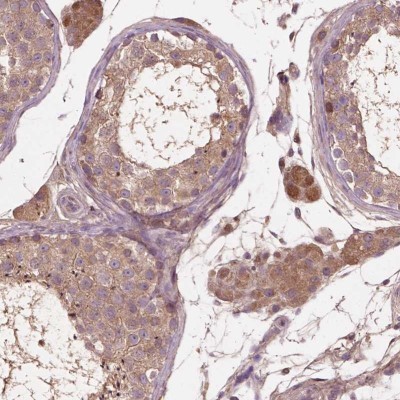

- Immunohistochemistry-Paraffin: Connexin 58/GJA9 Antibody [NBP2-39088] - Staining of human testis shows moderate cytoplasmic positivity in cells in seminiferous ducts and Leydig cells.